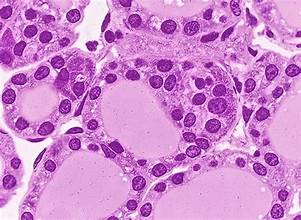

Функции и развитие почки, дефекты развития. Кровоснабжение почки. Почечное тельце:фильтрация. Подоциты и фильтрационный барьер. Мезангий

Нефрон: строение и реабсорбция в разных отделах. Юкстагломерулярный аппарат. Эндокринная функция почки. Регенераторный потенциал. Мочевыводящие пути. Уротелий

Структурная организация мозгового и коркового вещества почки, мочевыводящих путей